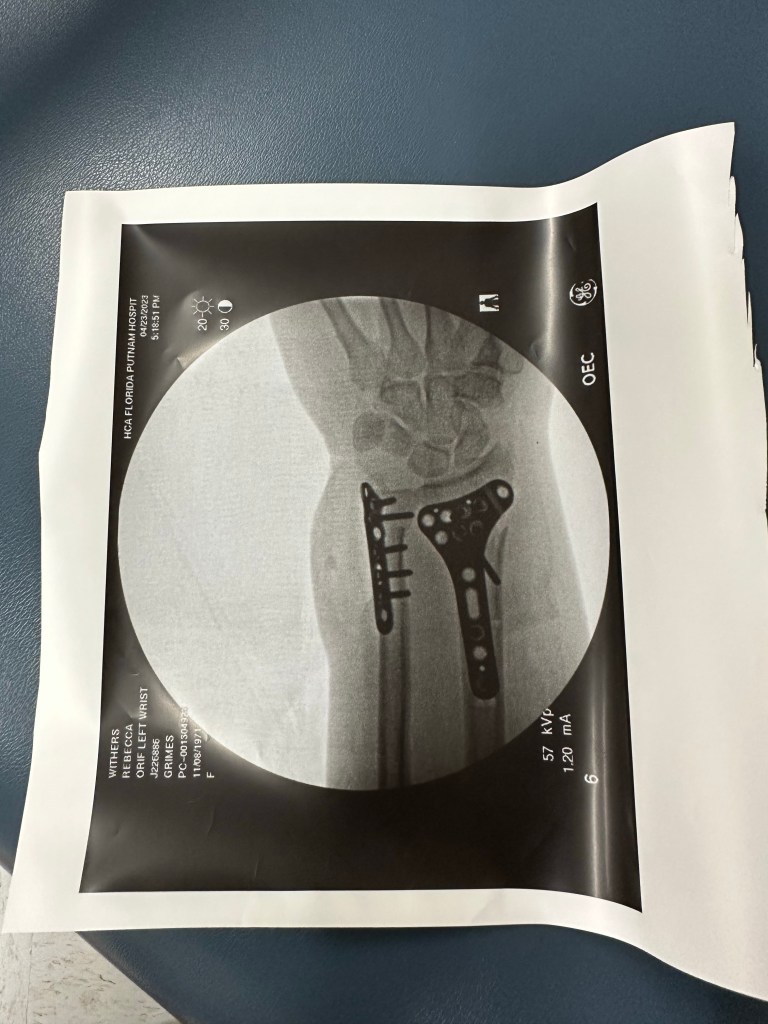

The last 24 hours have been terrifying and amazing all at once. How can that be? Because God is good! We’ve had a lot going on, on my side of the family lately, I broke my wrist, not paying attention on a boat, April 22. I had to have emergency surgery and now I have two metal plates and nine screws in my left wrist, goooo me!